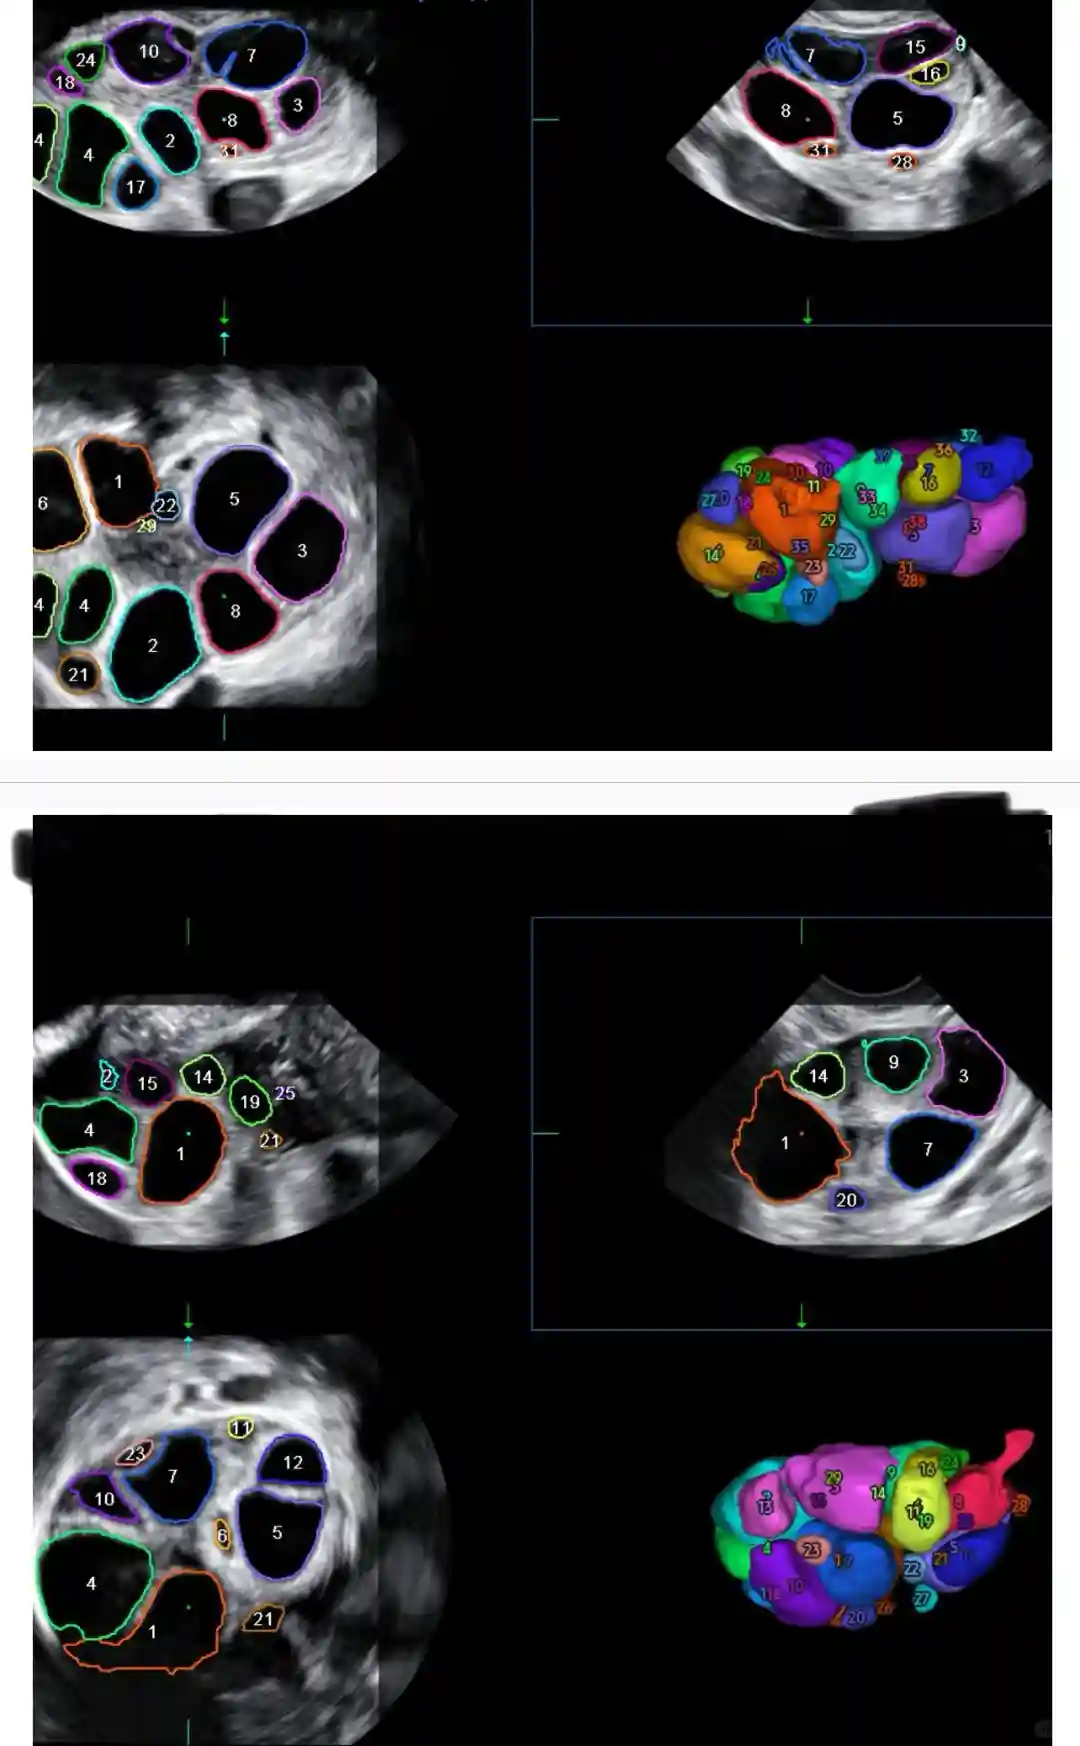

图89,10,打了9天Gonal-F和6天Fyremadel验血及B超结果